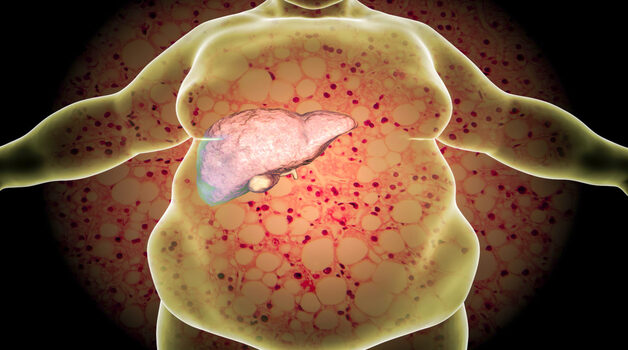

Bệnh gan nhiễm mỡ có thể làm tăng nguy cơ ung thư gan hoặc các loại ung thư khác, bao gồm ung thư đại trực tràng. Nhiều người mắc gan nhiễm mỡ cũng có các yếu tố nguy cơ ung thư khác, chẳng hạn như béo phì.

NAFLD xảy ra ở tới 90% người béo phì. Tình trạng này có thể tiến triển thành một dạng nghiêm trọng hơn gọi là viêm gan nhiễm mỡ không do rượu (NASH), liên quan đến viêm và tổn thương gan.

NAFLD có thể đảo ngược bằng thay đổi lối sống như:

Tập thể dục nhiều hơn

Ăn uống cân bằng

Giảm cân nếu thừa cân hoặc béo phì

Gan nhiễm mỡ thường được coi là ”bệnh thầm lặng” vì thường không gây triệu chứng cho đến khi tiến triển nặng. Bạn có thể đảo ngược một phần tổn thương gan bằng cách ngừng rượu (đối với AFLD) hoặc cải thiện chế độ ăn và tăng vận động (đối với NAFLD).